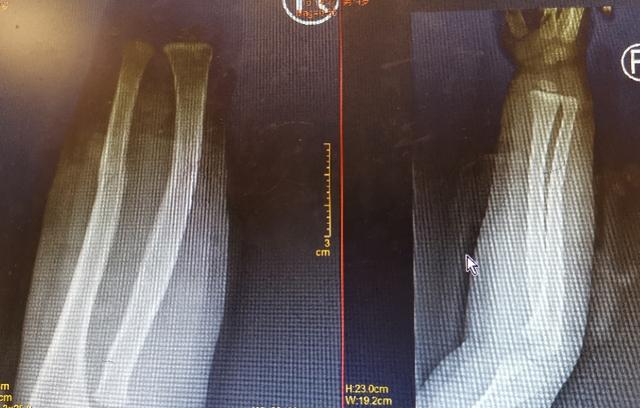

骨科医生李煜首先仔细看了片子,发现小明的右尺骨和桡骨骨折。和家人充分沟通后,他说孩子还小,麻醉和手术风险巨大。同时手术复位容易留下疤痕,对孩子来说是难以承受的痛苦。但是小明的伤情严重,医生的复位技术要求极高。

照片显示骨折。

复位后,x光片显示骨折几乎完全复位。